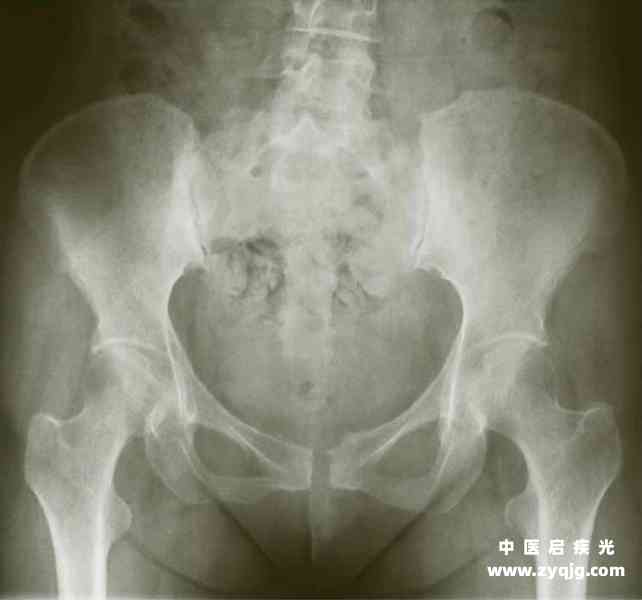

2.慢性损伤 多见于长期弯腰工作、经常过度负重或脊柱疾病,可促使骶髂关节退行性变,久而久之骶髂关节错位、关节密度增高(图4-31)。

4-31 骶髂关节密度增高

3.辅助检查X线检查可有骨盆形态改变,部分患者有患侧骶髂关节间隙增宽,耻骨联合分离或上下错移。陈旧性损伤可见骶髂关节下缘骨质增生,关节面毛糙或骨密度增高影。

2.强直性脊柱炎 多见于男性青年,脊柱强直出现较早;脊柱前屈、侧弯、后仰活动受限。X线检查表现为骶髂关节密度增高,椎体轮廓模糊,呈竹节样改变,小关节间隙模糊。骶HLA-B27多为阳性。